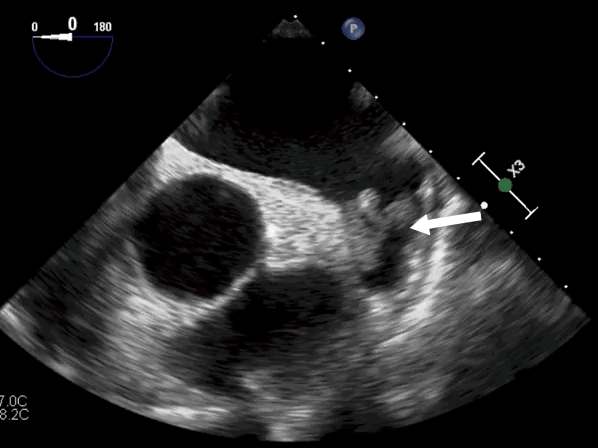

Если мы введем датчик и там действительно есть тромбы, то мы увидим примерно такую картину:

Тромбы в ушке левого предсердия. Стрелка указывает на тромбы.

Источник: https://edu.euat.ru/study/view?id=283